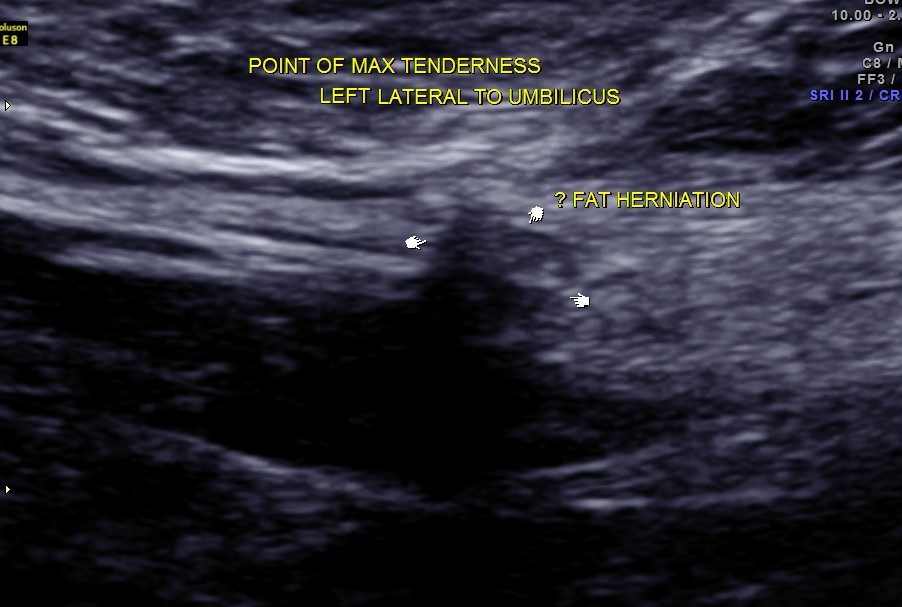

She came with history of localised pain to the left of the umbilicus for the past 18 days.

Scan with high resolution probe over the point of maximal tenderness revealed peritoneal fat herniation.